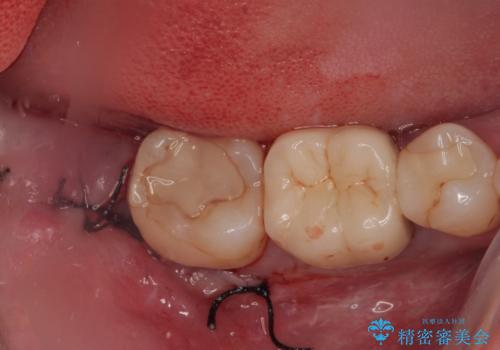

右下の親知らずを抜きたい 親知らず抜歯

担当医 有澤哲郎